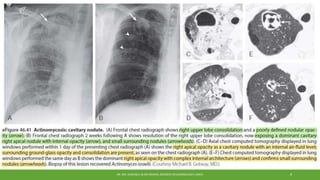

Imaging

•Classic finding for actinomycosis is direct extension of a cavity or mass through

an interlobar fissure.

•Commonly, changes are confined to a single lobe with consolidation, nodules,

one or more small cavitary lesions.

•Pleural thickening or effusions are also encountered.

•Advanced cases, the findings may be more distinctive, with penetration

through the chest wall and/or destruction of adjacent bone tissue.

•CT imaging may reveal bone erosion.